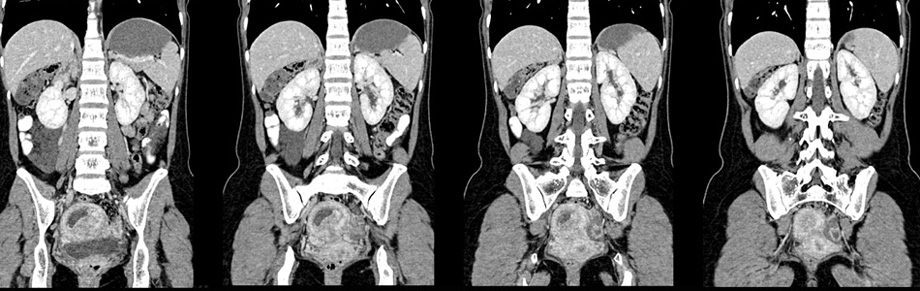

女性,28岁,停经3月,腹部膨隆1月,产前检查发现腹部占位

{肿块中心ct值27hu,增强后,动脉期、门脉期均无明显强化)

患者手术病理:腹腔囊性淋巴管瘤,象这样充满整个腹腔的的确很少见